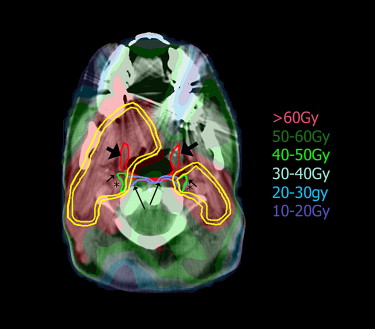

Targets (clinical target volumes [CTVs] and their respective planning target volumes; yellow) in relationship to the retropharyngeal (RP) nodes and the pharyngeal constrictor (red; thick arrows marking its anterior edges). The CTVs encompass the lateral RP nodes (green; short arrows), outlined in the retropharyngeal space medial to the carotid arteries (marked by asterisks). The CTVs do not include the medial RP nodes (blue; long arrows).